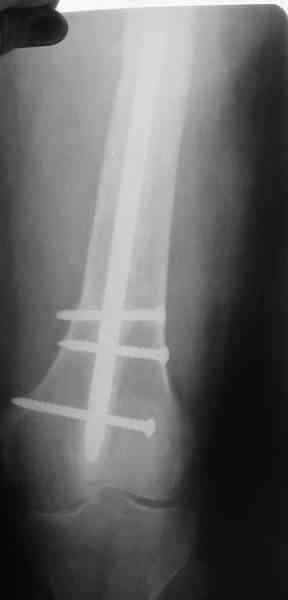

1, 2, 3, 4 - рентгенограммы бедра от 8 августа этого года (через четыре месяца после операции);

4, 5, 6 - рентгенограммы бедра и фотографии пациентки (прошу прощения за низкое качество рентгеновских снимков) от 7 сентября 2007 г.